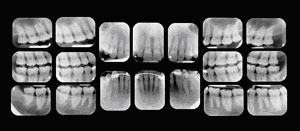

Regular checkups include a thorough cleaning, polishing, and an oral exam by the doctor. During the oral exam, the doctor checks the health of your mouth, teeth, gums, cheeks, and tongue. At each visit, the doctor also checks old fillings and restorations because constant pressure from chewing, grinding, or clenching can cause them to wear away, chip, or crack. Your First Visit Your first visit to the doctor typically includes an x-ray that allows the doctor to view the structure of the jaw, the position of any teeth that have not yet erupted, malformed roots, and tooth decay. ![]() The initial visit also involves getting your medical history. When you share your medical history with the doctor, be sure to provide complete, up-to-date information on your health. Inform your dentist if you have experienced recent hospitalization or surgery, or if you have recently been ill. Also tell the doctor the names, doses, and frequency of any medications you are taking — whether prescription or over-the-counter products — and the name of your physician. Inform the doctor of any changes in your health or medications. It is also important to bring up any fears you may have about dental treatment. The information collected in your first visit will help the doctor select the safest and most effective method of treatment for you. |